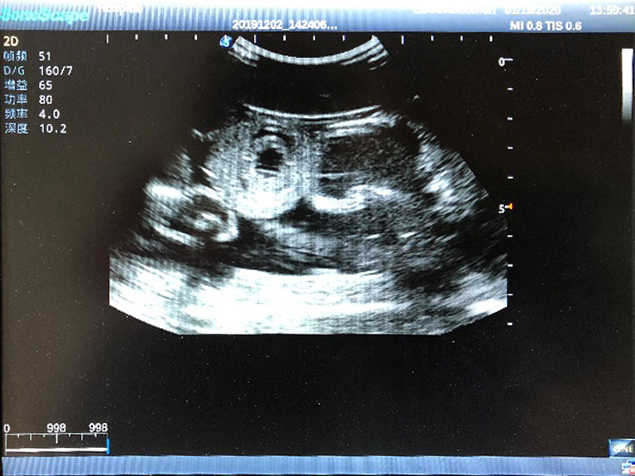

2)  High quality ultrasound image with clear structures like gallbladder, liver, intestines, arteries and veins etc.